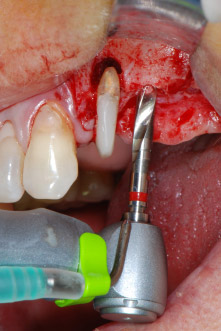

Antes de colocar el implante, el tejido infectado del hueso alveolar ubicado en el lugar del implante y alrededor de los dientes del pilar se retiró con un inserto concebido en un principio para modelar huesos y recoger virutas óseas: Piezomed y el inserto B5 (figuras 6 y 7).

instrumento de raspado piezoeléctrico

Fig. 6: A continuación, el sitio quirúrgico se desbridó con un instrumento de raspado piezoeléctrico diseñado para recoger virutas óseas y modelar el hueso.

defectos óseos

Fig. 7: Después de la limpieza, se apreciaban claramente los defectos óseos en el área mesial de la pieza 27 y alrededor de la pieza 24.